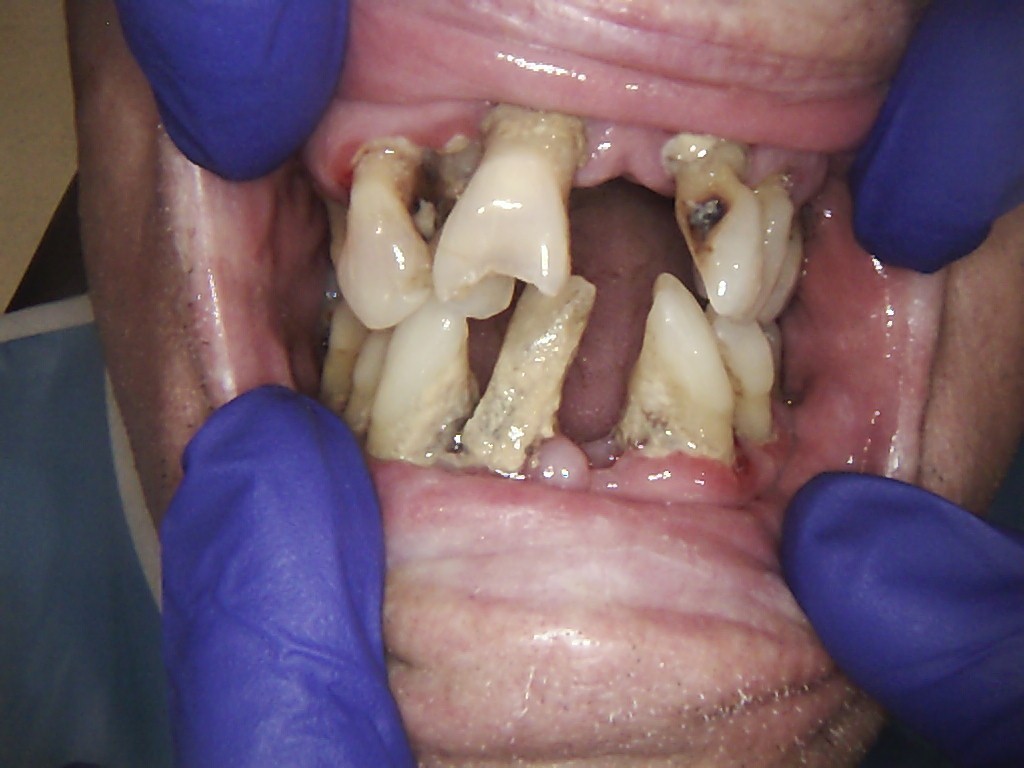

Examples of our work.

Full Mouth Case with Snap-on-Locator Dentures